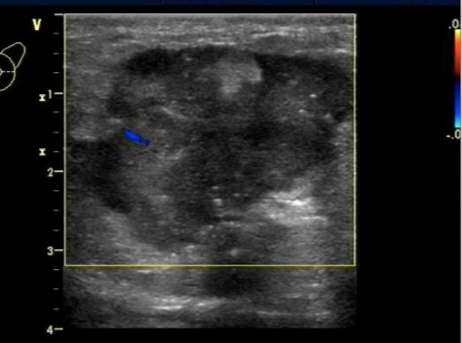

4.乳腺结节的内部回声。

分为:无回声、低回声、等回声、高回声和混合性回声。不均匀低回声的结节多为恶性,混合性回声多为囊实性结节,其恶性的可能>10%。

乳腺恶性肿瘤彩超表现,乳腺结节良性恶性彩超对照图

结节内回声不均,术后病理为恶性